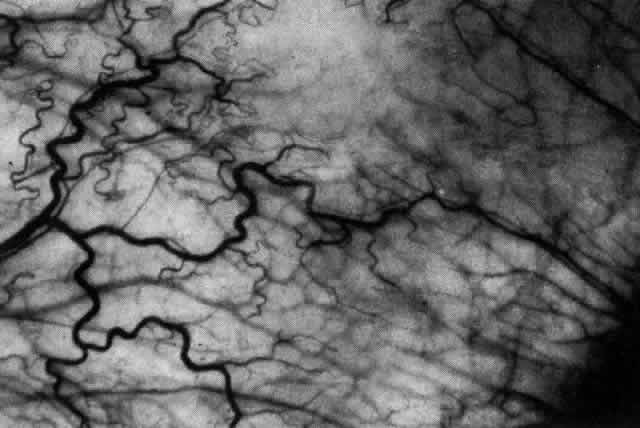

What is clinically represented solely by inflammation and edema is histopathologically a granulomatous lesion of the sclera, the center of which consists largely of plasma cells, lymphocytes, and mast cells (Figs. 21 through 23). Foster and colleagues have identified the cellular subsets and glycoproteins in both necrotizing and non-necrotizing scleritis.22 This shows an active T-cell inflammatory response with a high CD4/CD8 ratio and increased HLA/DR and CD14, indicating a macrophage-induced response that would lead to granuloma formation. Remote from the granuloma, the fibrocytes of the sclera become activated, the proteoglycan adjacent to them becomes altered, and the collagen fibrils of the sclera become unraveled (Figs. 23 and 24). These changes appear to take place prior to the invasion of the stroma by cells of the granuloma.20 The vessels in and around the necrotic area show medial necrosis and perivascular cuffing with lymphocytes, and endothelial swelling with microvascular occlusion. Ninety-six percent of the specimens examined by Foster and associates show a microangiopathy characterized by a neutrophil infiltrate in and around the vessel wall.22–23 This is most obvious at the center of the lesion where there may be occlusion of the vessel, thrombosis, or even aneurysm formation (Fig. 25). From these pathologic investigations, clinical observations, animal experiments, and the results of fluorescein angiography, it would appear that the scleral inflammation is initiated either by trauma (be it accidental or surgical)23–25 or by bacterial or viral infection. If circulating immune complexes are present because of the poor blood flow, they become precipitated in and around the vessel walls in the area of inflammation. In other patients, a persistence of tissue damage will lead to autoimmunization. Damage to the endothelial cells of the microvasculature leads to changes within the vessels detectable on angiography and to catabolic changes in the surrounding tissues. These changes, in turn, allow the granulomatous response that is seen in histopathologic sections, the first detectable change being in the scleral fibrocytes and the proteoglycan and collagen remote from the site of cellular infiltration.

Fig. 21. Advancing edge of a granulomatous reaction. Scleral fibers are split and separated by edema and then disrupted when invaded by the granuloma

Fig. 22. Electron micrograph of an area of active scleritis showing the plasma cell infiltrate suggestive of an immune response. Note aggregated plasma cells, with the characteristic whorled rough endoplasmic reticulum, in the process of degeneration, releasing organelles and nuclear debris into the extracellular matrix. (Uranyl acetate and lead citrate. X3000) (Courtesy of Dr. R. Tripathi)

Fig. 23. Electron micrographs of scleral stroma at the periphery of an area of ulceration in a patient with necrotizing scleritis. The left shows an active fibroblastic cell, and the right shows collagen fibrils within intracellular vacuoles (V) in the fibroblastic cell. (Left X15,375; right X15,375) (Watson PG, Young RD: Changes at the periphery of a lesion necrotizing scleritis: Anterior segment fluorescein angiography correlated with electron microscopy. Br J Ophthalmol 68:781–789, 1984)

Fig. 24. Electron micrograph of scleral stroma at the periphery of an ulcer in necrotizing scleritis (same patient as in Figure 23) showing swelling and unraveling of collagen fibrils (arrows) in longitudinal section (X29,270) and in transverse section (inset, X44,000). Fibrils of all diameters are affected. (Watson PG, Young RD: Changes at the periphery of a lesion necrotizing scleritis: Anterior segment fluorescein angiography correlated with electron microscopy. Br J Ophthalmol 69:656–663, 1985)